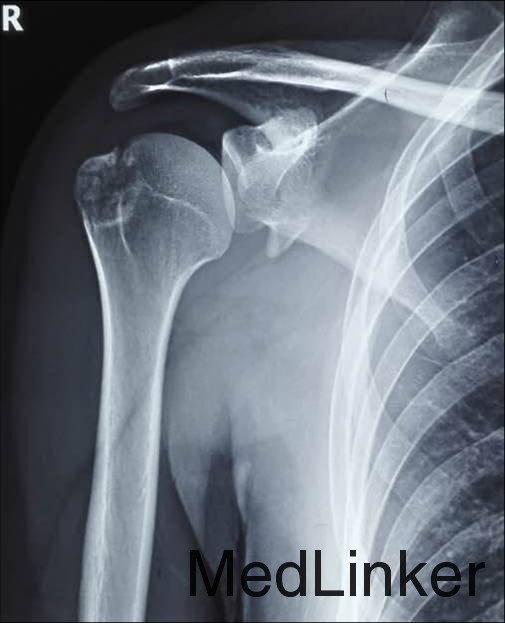

患者谢某某,男性,28岁,已婚 患者坠马后摔伤右肩部,局部肿痛伴活动受限7日 外院就诊摄片示:右肩胛骨折;右肱骨大结节骨折 右上肢外展支架外固定

查体:右上肢穿戴外展外固定支架,右肩关节局部软组织明显肿胀,肤色正常,皮温正常;局部压痛明显,尤以右肩胛骨上缘,以及右肱骨大结节处疼痛明显,疼痛以刺痛为主;右肩关节主动前屈、后伸、内收、外展、上举活动受限,内旋约0°-60°,外旋约0°-15°,被动活动肩关节疼痛明显加重;右肘、腕关节活动正常,右手各指末梢血运、感觉及活动正常

右肩甲盂骨折